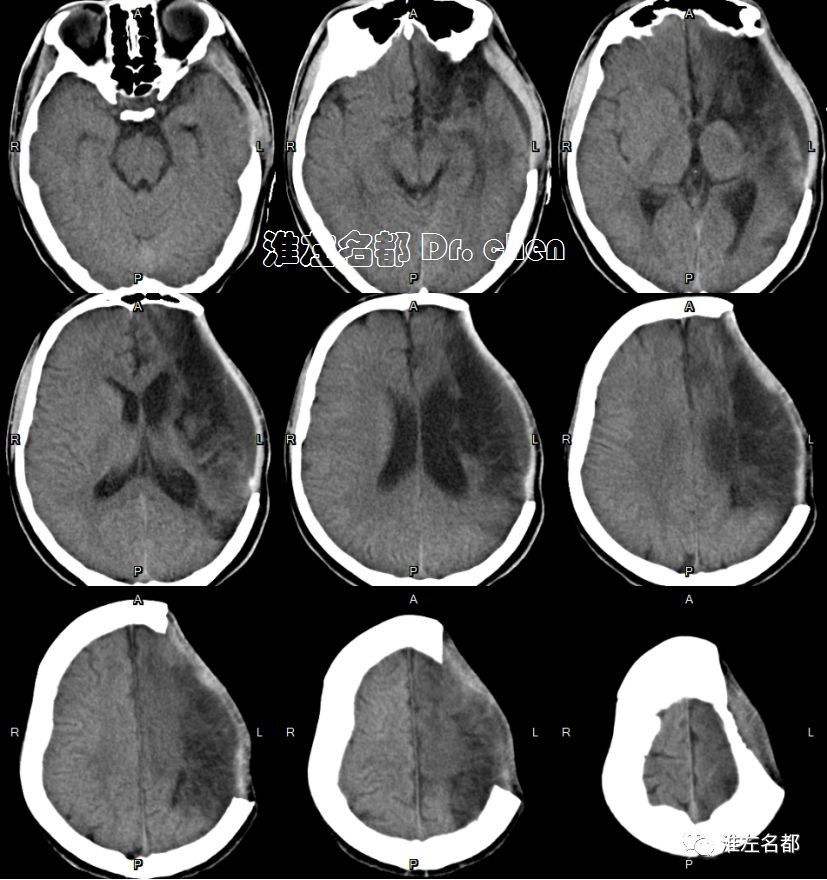

急诊多模式CT

△头颅CT平扫:左侧半球大范围低密度,灰白质分界消失,脑沟受压变小-消失;左侧大脑中动脉区ASPECT-2。

复查CT

2019-9-1 11:34

△颅脑CT平扫+增强:左侧基底节区和部分额叶呈稍高密度,左侧前循环血流通畅;左侧半球肿胀明显,脑室、脑沟和脑池受压,中线结构向右侧显著移位。